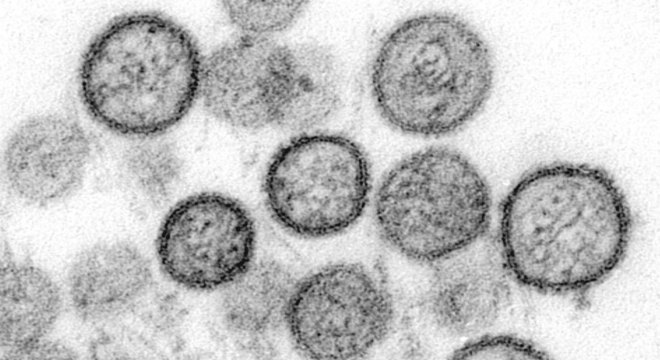

Não há tratamento específico para a hantavirose e quase quatro a cada dez pessoas morrem após a contrair a doença Getty Images / BBC NEWS BRASIL

A hantavirose é uma doença viral grave transmitida por roedores. É comum que sejam registrados casos de contágio por hantavírus a cada ano em países da América do Sul, inclusive o Brasil. Mas um surto fatal da doença no sul da Argentina tem chamado a atenção.

O mais comum é que o contágio ocorra diretamente pela inalação de partículas de urina, fezes e saliva de roedores silvestres – não pelo contato com outros humanos infectados. Por isso, os casos da doença costumam ser isolados. Diferentemente dos seres humanos, roedores, como ratos e ratazanas, podem carregar o hantavírus por toda a vida sem adoecer.

A hantavirose gera sintomas parecidos com uma gripe: febre, dores musculares, calafrios, dores de cabeça, náuseas, vômitos, dor abdominal e diarreia.

Mas, depois de alguns dias, o quadro se agrava e surgem dificuldades respiratórias que desembocam na chamada síndrome cardiopulmonar por hantavírus.

Neste caso, as pessoas passam a ter febre, dificuldade de respirar, respiração acelerada, aceleração dos batimentos cardíacos, tosse seca, pressão baixa, e edema pulmonar não cardiogênico. É possível, neste caso, que o paciente evolua para insuficiência respiratória aguda e choque circulatório.

Segundo Organização Mundial da Saúde (OMS), a taxa de mortalidade dessa doença é de 38% e não há um “tratamento específico” para ela.